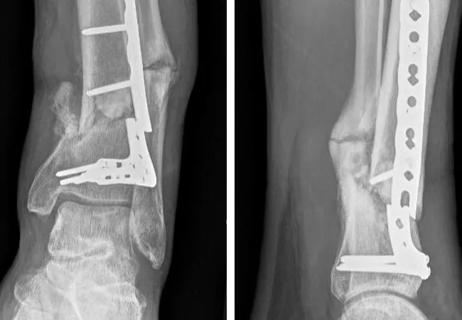

Reconstructing Nonunions of the Distal Tibia

Approaching distal tibial nonunions